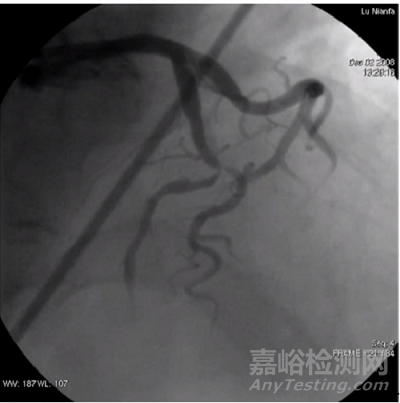

冠狀動脈疾病(CAD)是全球致死率最高的疾病之一,其中冠脈分叉病變占據了相當一部分比例。根據多項研究數據,冠脈分叉病變約占PCI(經皮冠狀動脈介入治療)治療病變總數的15-20%。這一病變的復雜性和不確定性導致了臨床治療中的許多挑戰(zhàn),尤其是在進行藥物治療時。

分叉病變的形態(tài)多變,包括血管角度、斑塊分布以及血管直徑等因素,常使得傳統(tǒng)的冠脈介入治療方法效果有限,甚至可能增加治療失敗的風險。

藥物涂層冠脈球囊(DCB)作為一種“介入無植入”的治療方式,被視為治療分叉病變的潛力解決方案,尤其在避免支架植入的情況下,它的療效和安全性得到了廣泛關注。

AcoArt Canna®是先瑞達推出的公司首款西羅莫司藥物涂層冠脈球囊擴張導管,它是針對分叉病變的一項創(chuàng)新產品,代表了先進的藥物涂層技術。這款產品將用于治療血管直徑≥2.0mm且≤4.0mm的原發(fā)冠狀動脈分叉病變狹窄,進一步拓展了先瑞達在冠脈介入領域的技術實力,并標志著公司在全球藥物涂層技術方面的領先地位。